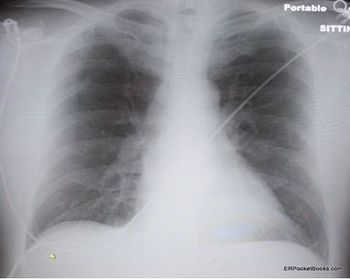

Drug-induced hypersensitivity pneumonitis, drug-induced organizing pneumonia, radiation-induced lung injury, allergic fungal rhinosinusitis, pulmonary tuberculosis, empyema-this week’s slide show sheds light on several presentations.

Pulmonary edema, tracheal stenosis, pulmonary embolism, pulmonary sarcoidosis, respiratory bronchiolitis interstitial lung disease, giant bullous emphysema-a close look at a variety of troublesome lung conditions.